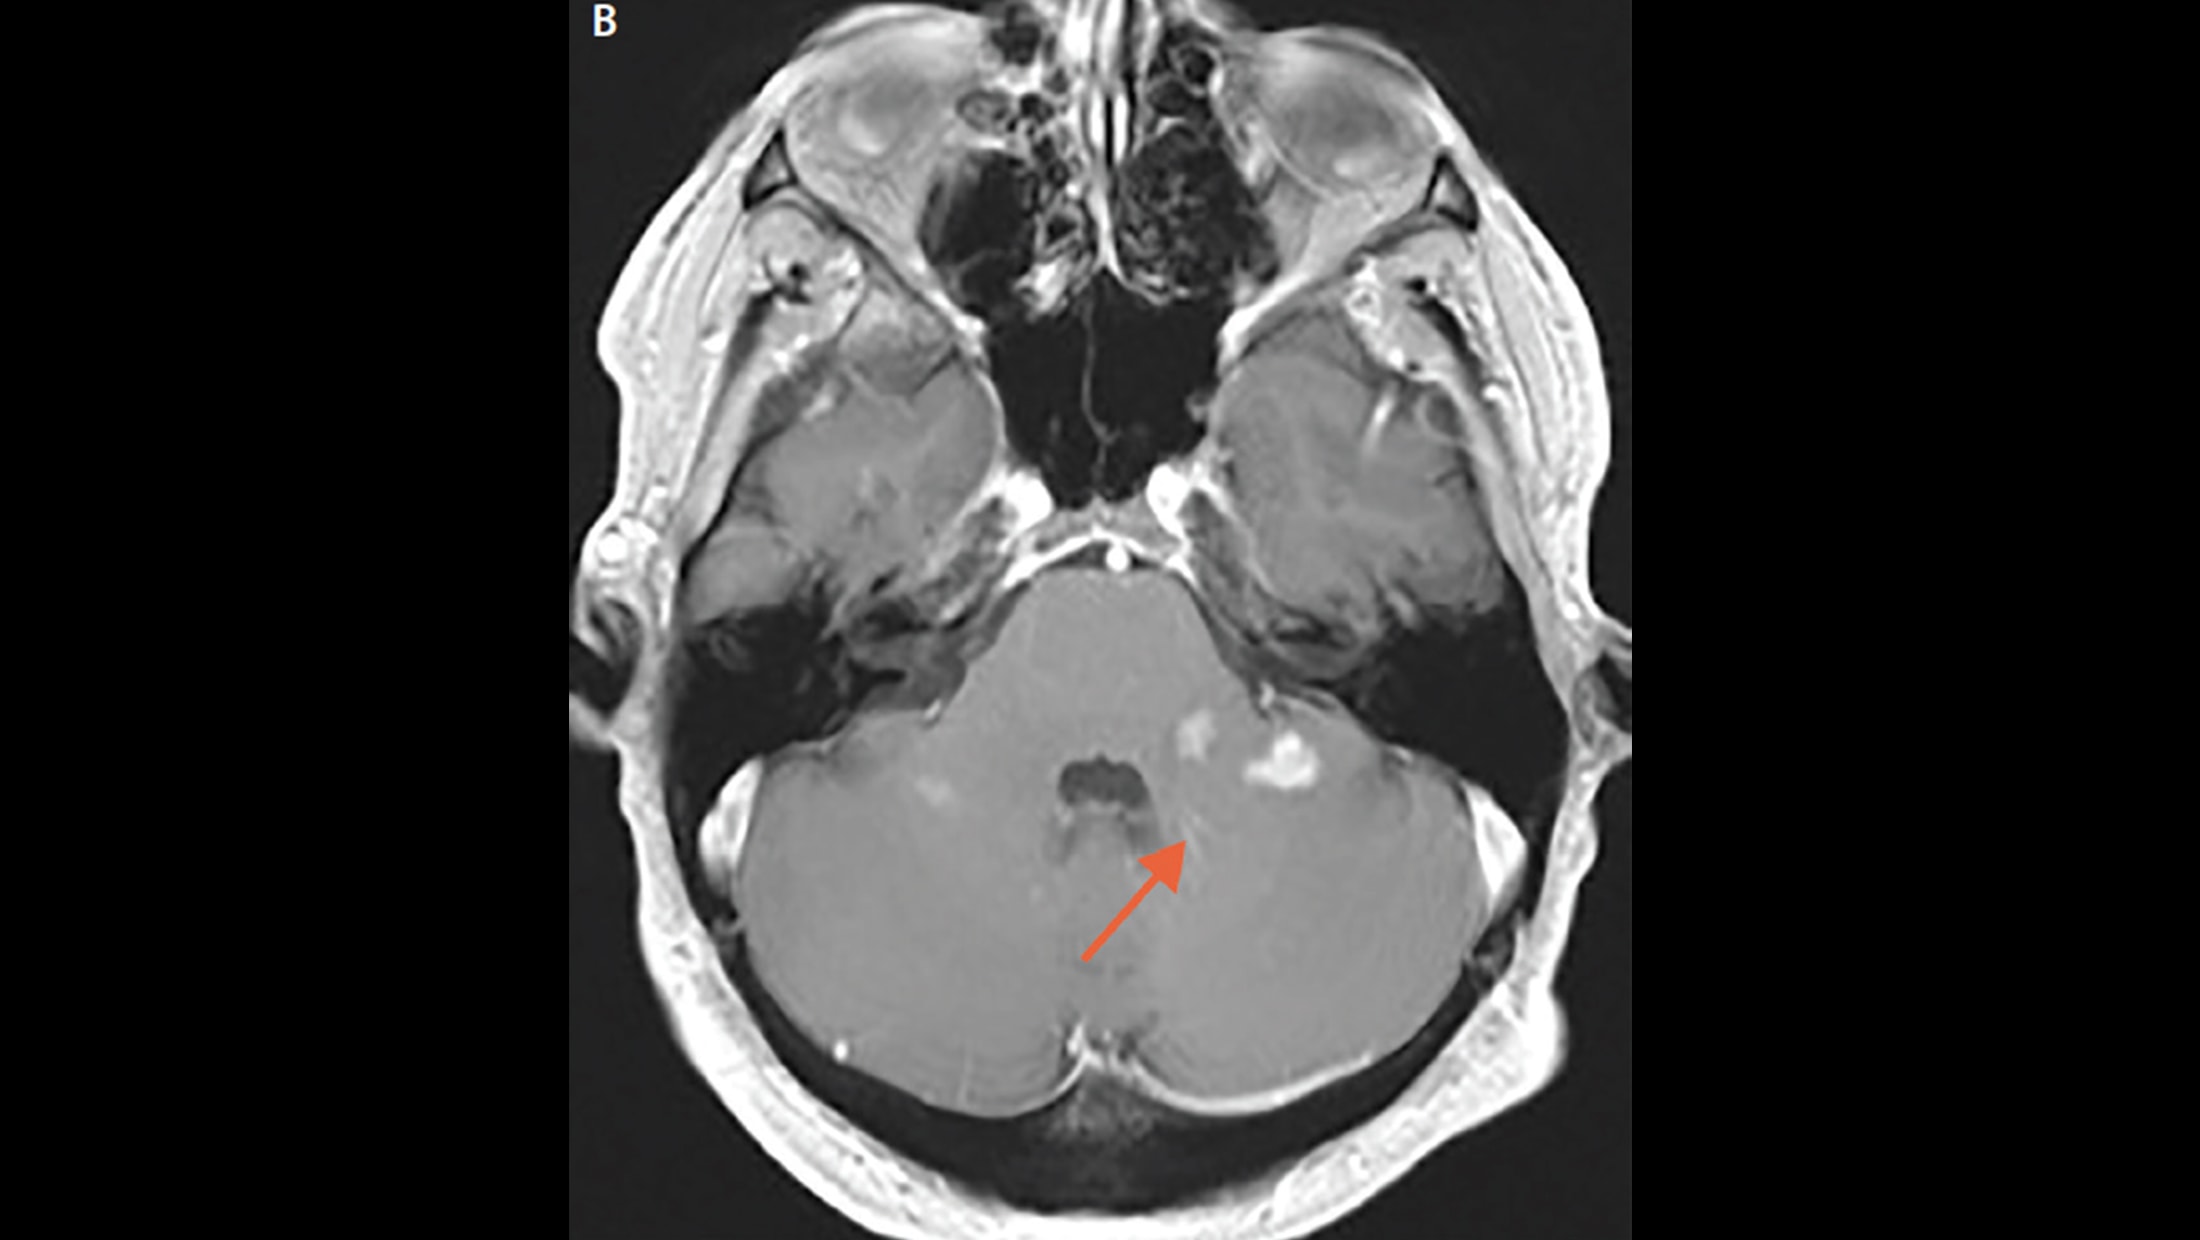

MRI showing showing a lesion at the optic tract (arrow) and surrounding Optic Tract Lesion Rapd Hence lesions of pretectum produce rapd in the contralateral eye. The optic tract lesion is a unique pathological entity because it results in a homonymous hemianopsia. The main sign of marcus gunn syndrome is having one pupil that does not constrict properly in response to light. Most often, patients have an ocular or medical history that might explain its presence.. Optic Tract Lesion Rapd.